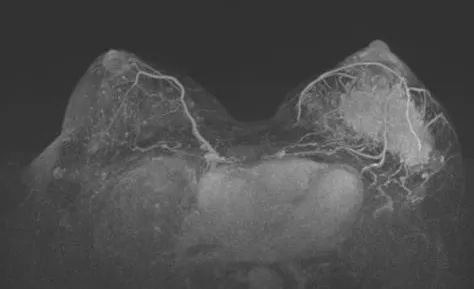

2021-11 乳腺MRI:左乳上份、外上象限见一不规则等T1,等-稍长T2信号肿块,大小约8.2cm×3.7cm×6.5cm,ADC值最低处0.71×10E-3mm2/s,动态增强扫描不均匀显著强化。左腋下多枚肿大淋巴结,大者约2.2cm×1.3cm,增强明显不均匀强化。形状呈不规则,边界欠清楚。

图2. 新辅助治疗前乳腺MRI

图3. 上图为治疗前,下图为治疗6周期后

治疗6个周期后,乳腺增强MRI显示靶病灶明显缩小,临床疗效评估为PR;腋窝靶病灶消失,临床疗效评估为CR。